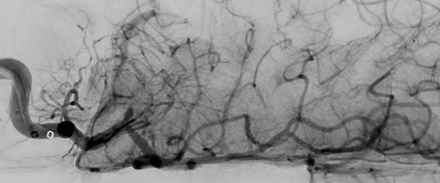

封面图片:图像显示一名8岁儿童中风患者行取栓后再灌注不成功。由Kaitlyn Aman Ramm,高级数字多媒体/图形协调员编写。看到页面e1148